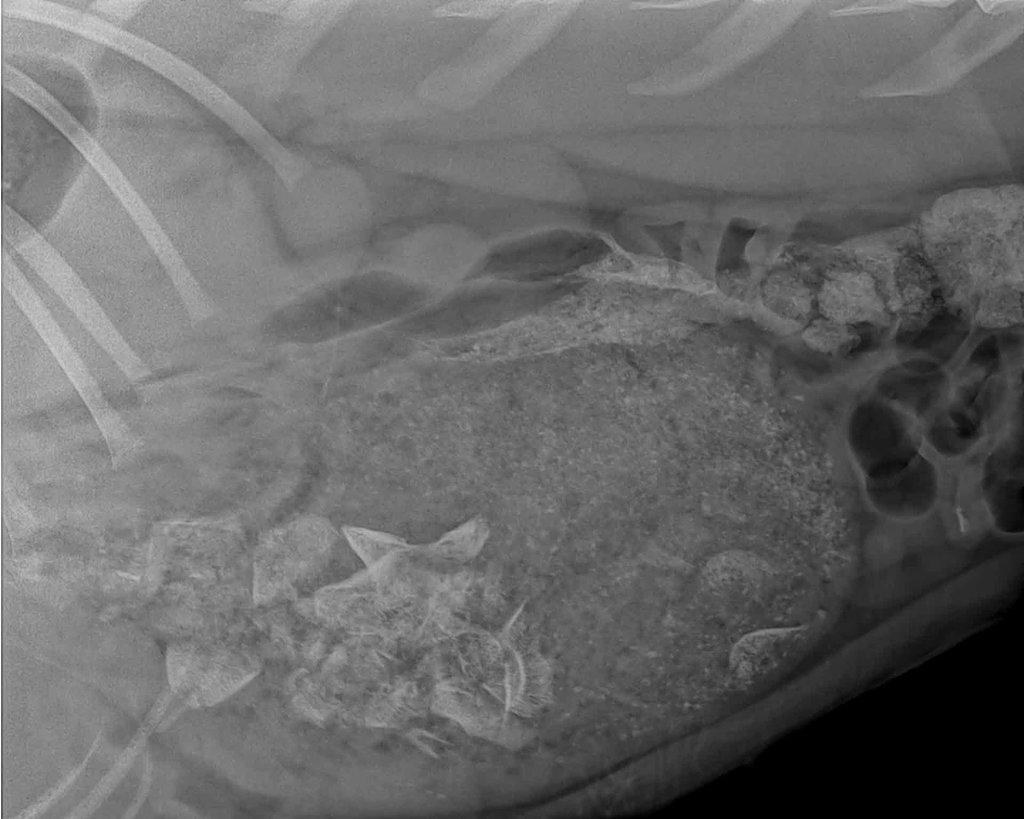

Aurora was a bit feistier than Rainbow when she arrived and was not in too bad of overall condition.  She was bloated from being fed too much and had her claws cut really short, but the main thing was that she seemed very frightened. After spending a night in our quarantine pen, Aurora was anesthetized and given a full health check to make sure she was healthy, remove any parasites, and give her relevant vaccinations without stressing her out. The next morning we decided it was time to introduce her to Rainbow, as the sooner the two cubs were together the better it would be for them.